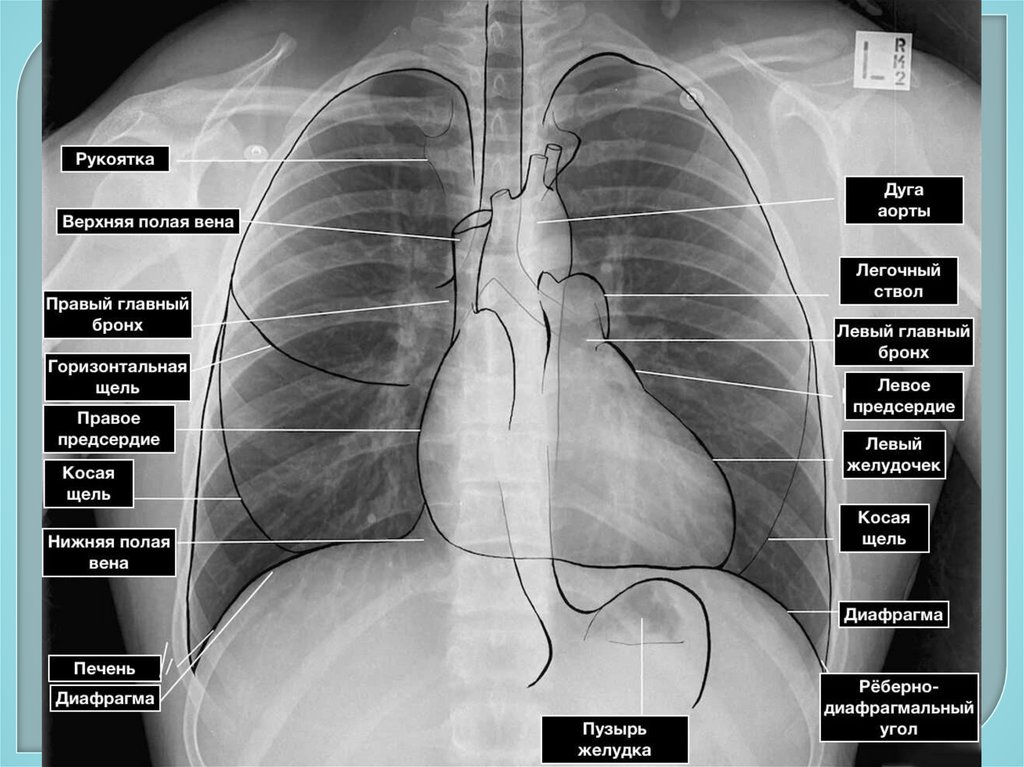

101. Дополнительное обследование

Инструментальные методы:

1. Рентгенологические методы –

рентгенография грудной клетки,

флюорография, бронхография,

компьютерная томография